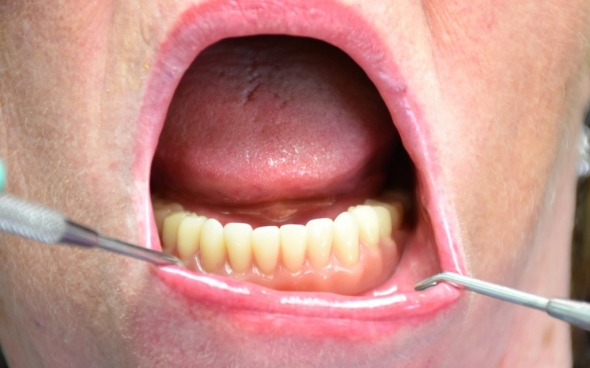

Unterkiefer Locator-Prothese auf 4 Implantaten

Die 82 jährige Dame aus der Schweiz meldete sich mit zwei Restzähnen im Unterkiefer, mit dem Wunsch nach festem Zahnersatz. Der Zustand der Zähne und der vorhandene Abszess machten die Extraktion erforderlich. Das Knochenangebot erwies sich im Unterkiefer als ausreichend für eine implantatgetragene Versorgung.